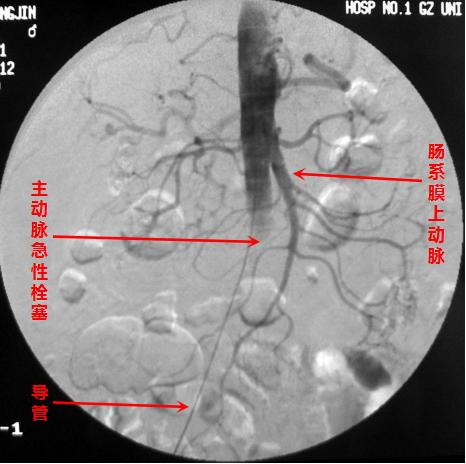

主动脉急性闭塞,相对少见

动脉被堵而出现缺血,这个好理解。因为动脉不能向器官组织顺利地运送富含氧气和营养物质的动脉血了嘛!器官组织对缺血缺氧常常会以疼痛来作“警示”,比如心脏冠状动脉缺血会出现心绞痛,下肢缺血会出现患肢的剧烈疼痛,肠系膜动脉堵塞也会出现腹痛。随着缺血程度的加重,后续可能引起心肌梗死、肢体冰凉、肠道坏死等严重后果,并均可危及生命。

首先,通过介入血管插管,可以在远离病变、容易操作的部位简便实施。插入的细小导管可顺着血管走行,进行选择性血管造影,从而准确直观地显示出血管堵塞的部位、范围和程度,是诊断血管病变的“金标准”,为下一步的治疗提供有力的依据。

其一,经导管溶栓术。即通过导管在血栓内部注射适量的溶栓药物,如尿激酶等,一边注药一边推进导管,步步为营,将新鲜的血栓及时有效地溶解掉。这是一种比较简单、常用的方法,可以单独应用,也常与其他方法联合应用。